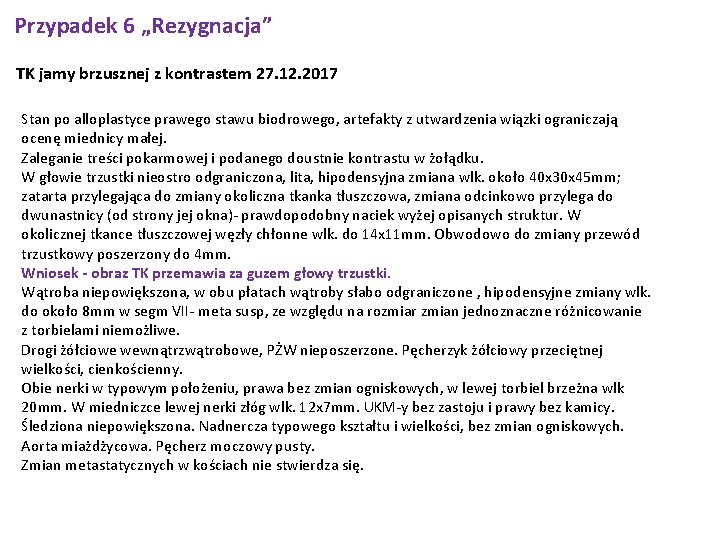

Przypadek 6 „Rezygnacja” TK jamy brzusznej z kontrastem 27. 12. 2017 Stan po alloplastyce prawego stawu biodrowego, artefakty z utwardzenia wiązki ograniczają ocenę miednicy małej. Zaleganie treści pokarmowej i podanego doustnie kontrastu w żołądku. W głowie trzustki nieostro odgraniczona, lita, hipodensyjna zmiana wlk. około 40 x 30 x 45 mm; zatarta przylegająca do zmiany okoliczna tkanka tłuszczowa, zmiana odcinkowo przylega do dwunastnicy (od strony jej okna)- prawdopodobny naciek wyżej opisanych struktur. W okolicznej tkance tłuszczowej węzły chłonne wlk. do 14 x 11 mm. Obwodowo do zmiany przewód trzustkowy poszerzony do 4 mm. Wniosek - obraz TK przemawia za guzem głowy trzustki. Wątroba niepowiększona, w obu płatach wątroby słabo odgraniczone , hipodensyjne zmiany wlk. do około 8 mm w segm VII- meta susp, ze względu na rozmiar zmian jednoznaczne różnicowanie z torbielami niemożliwe. Drogi żółciowe wewnątrzwątrobowe, PŻW nieposzerzone. Pęcherzyk żółciowy przeciętnej wielkości, cienkościenny. Obie nerki w typowym położeniu, prawa bez zmian ogniskowych, w lewej torbiel brzeżna wlk 20 mm. W miedniczce lewej nerki złóg wlk. 12 x 7 mm. UKM-y bez zastoju i prawy bez kamicy. Śledziona niepowiększona. Nadnercza typowego kształtu i wielkości, bez zmian ogniskowych. Aorta miażdżycowa. Pęcherz moczowy pusty. Zmian metastatycznych w kościach nie stwierdza się.